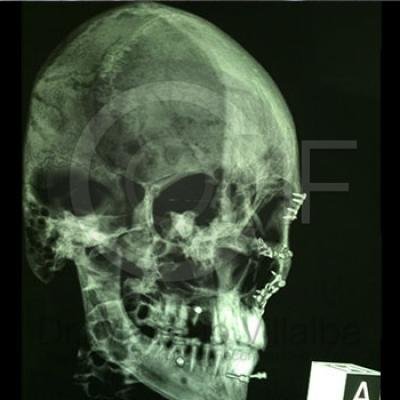

Fractura de Malar

Fractura De Malar Post1